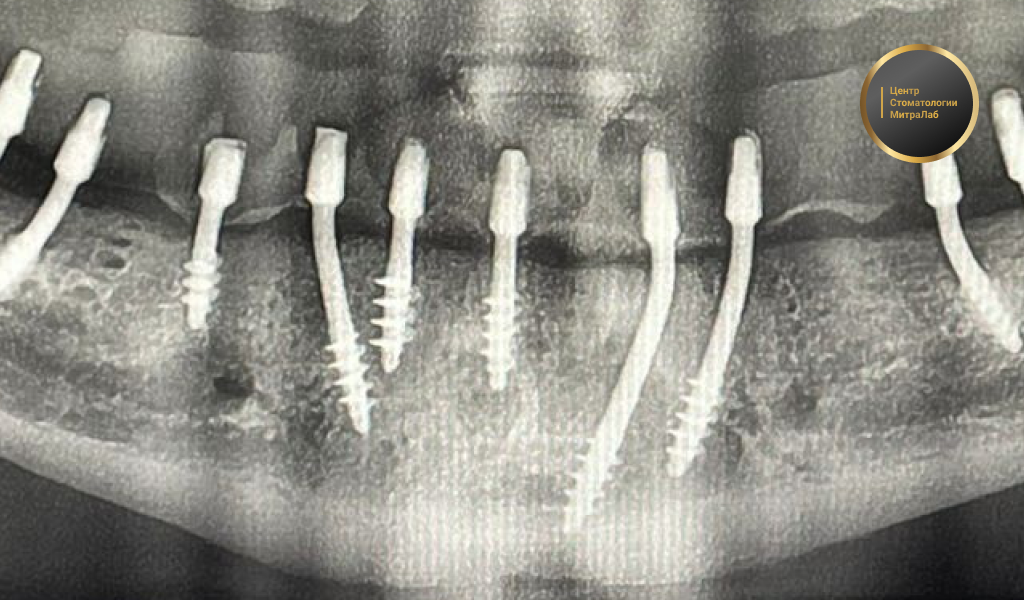

Один из наших давних клиентов увлекается хоккеем и во время игры ему в челюсть попала шайба. Несколько зубов были разбиты, а вот один из имплантатов лишь слегка погнулся. Врач МираЛаб восстановил нужный изгиб, зубы пациенту заменили новыми. Отметим, что операцию ему мы делали более 15 лет назад и до сих пор импланты отлично держатся.

Мы работаем со швейцарскими имплантами Доктор Иде Дэнтал Эй Джи (Dr Ihde Dental AG) и Уанвэй Биомед (Oneway Biomed). Они разработаны немецким профессором Стефаном Иде и признаны во всем мире. Это прочные и надежные конструкции из титанового сплава. Сломать их практически невозможно.